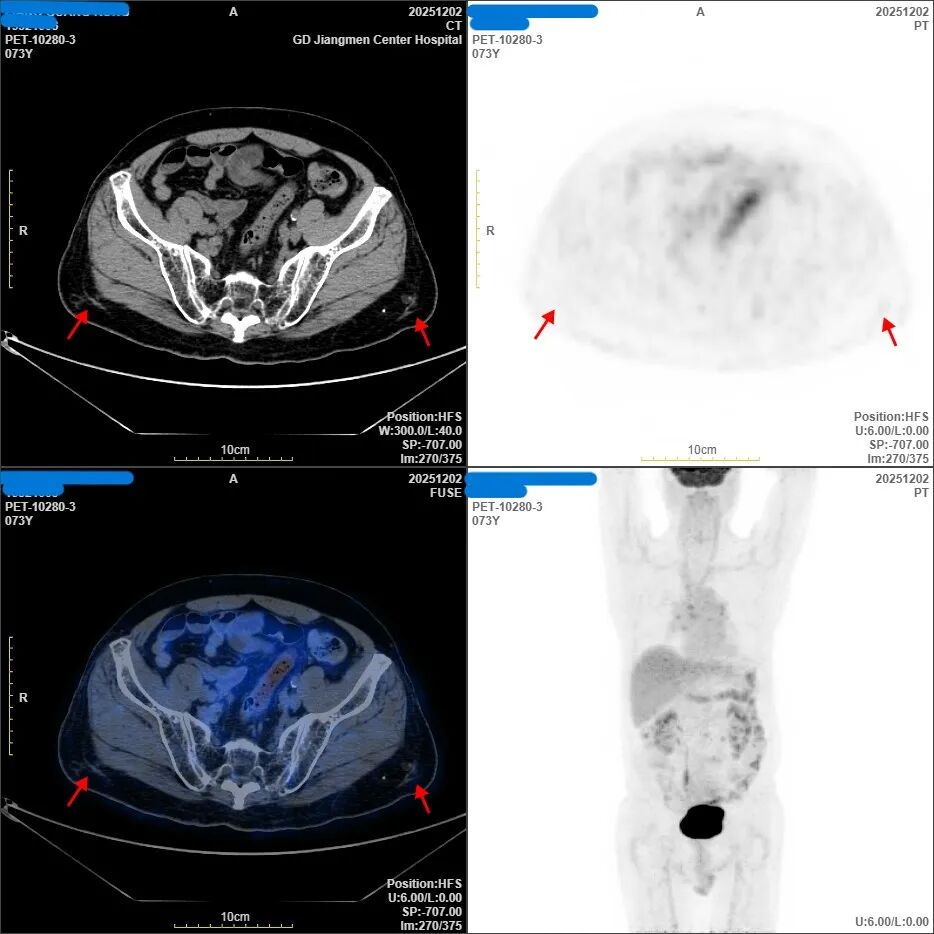

最终胜利:2025年12月,最新的PET-CT结果传来了最令人振奋的消息——全身肿瘤代谢活性病灶完全消失!疗效评价达到“完全缓解(CR)”。

这意味着,在梁伯体内已检测不到活动性肿瘤,在这场历时一年的生命突围战中,梁伯赢了!目前,梁伯精神饱满,食欲恢复,已回归正常生活,只需定期门诊随访。

第三阶段:放化疗后(后期评估)。原病灶区域代谢基本恢复正常,未见明显异常高代谢。